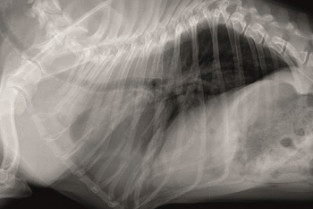

La section Ouest vous propose une soirée d'imagerie thoracique. A l'issue de cette soirée, le participant devra être capable de décrire l'aspect radiographique du mediastin, de l'espace pleural et des poumons. Il devra aussi être capable de localiser et qualifier les principales lésions thoraciques.

• décrire l'aspect du médiastin de l'espace pleural et des poumons en radiographie

• localiser et qualifier les principales lésions radiographiques thoraciques

Cas cliniques en imagerie